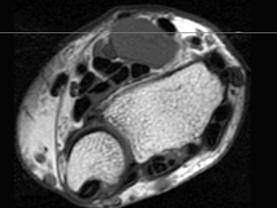

问题 男,69岁,腕部肿块1年,结合 图像,最可能的诊断是 ( )

选项 A、肌内脂肪瘤 B、未见异常 C、腕部腱鞘脓肿 D、腱鞘巨细胞瘤 E、腕部腱鞘囊肿

答案 E